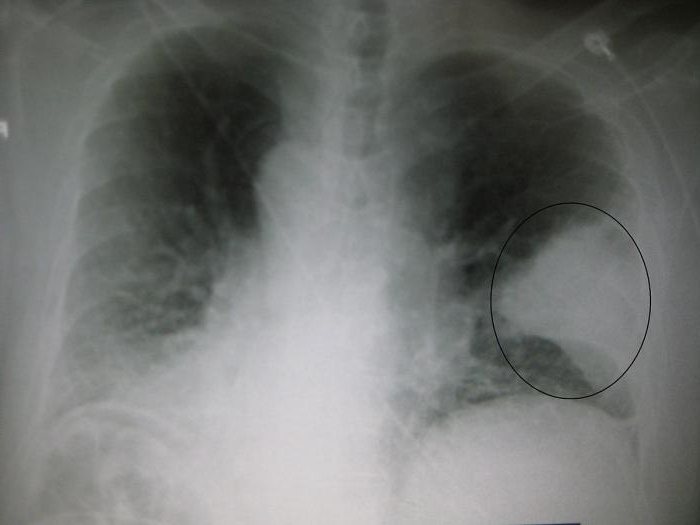

Рентгенологическое исследование

При подозрении на пневмонию человека отправляют еще и на рентгенологическое обследование. Этот метод дает возможность увидеть очаги поражения легких пневмонией. Эти патологические участки отражаются темным светом на снимке.

Есть еще и компьютерная томография. Она позволяет увидеть патологию в деталях, в самом ее зародыше. Это более точное обследование – даже небольшие рубцы от перенесенного ранее недуга не останутся незамеченными.